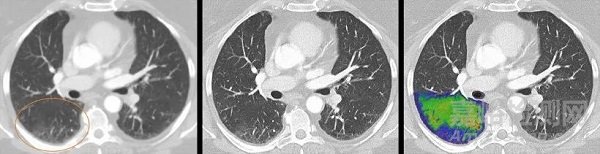

使用光子計(jì)數(shù) CT的新冠肺炎患者的肺圖像允許同時(shí)采集和可視化詳細(xì)結(jié)構(gòu)(中間)與功能信息(右圖)。對(duì)比傳統(tǒng) CT 技術(shù)獲得的圖像(左圖)

另外西門(mén)子還強(qiáng)調(diào)了該系統(tǒng)在腫瘤學(xué)和肺科方面的效用。

除了形態(tài)學(xué)的進(jìn)展之外,NAEOTOM Alpha 還提供了一種簡(jiǎn)單的方法來(lái)獲取定量信息。將所有必要的信息采集合并到一次掃描中,實(shí)現(xiàn)診斷路徑的智能導(dǎo)航。